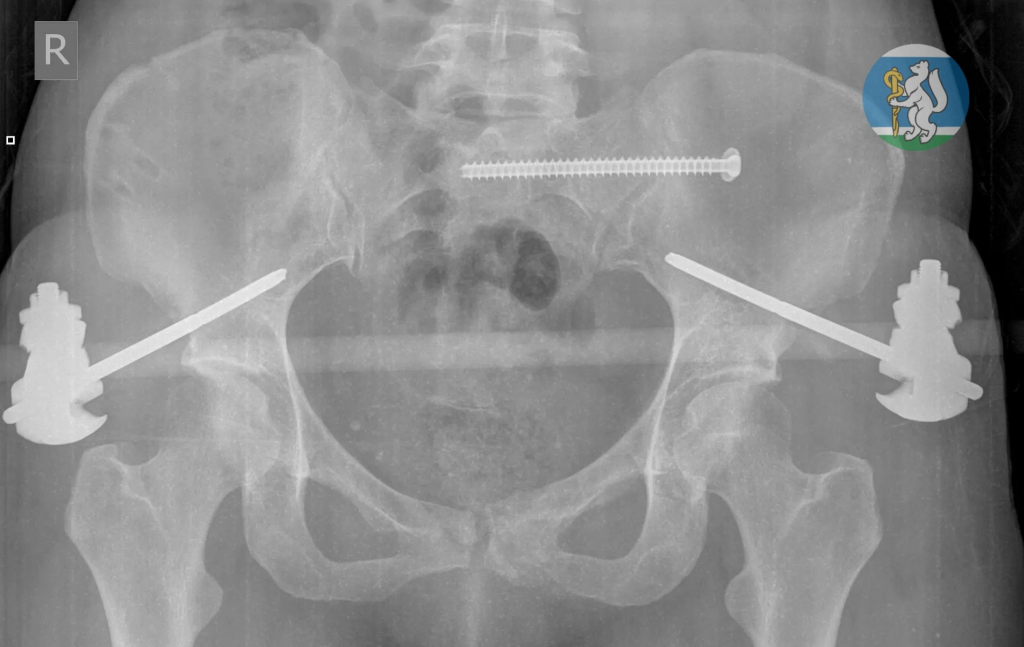

Когда бригада скорой помощи доставила упавшую с седьмого этажа свердловчанку в Городскую больницу №36 «Травматологическая», медики в результате обследования диагностировали у неё тяжелейшие повреждения: черепно-мозговую травму, повреждение шейного отдела позвоночника, множественные переломы костей таза, травму грудной клетки с повреждением лёгких, открытые оскольчатые переломы левой ноги. Большинство пострадавших с подобными травмами погибают ещё до приезда врачей.

После экстренной операции свердловчанка находилась в реанимации на искусственной вентиляции лёгких до полной стабилизации состояния. Через полторы недели её перевели в отделение травматологии, а ещё через две недели врачи успешно выполнили операцию по частичному демонтажу аппаратов внешней фиксации и синтезу сломанных костей.